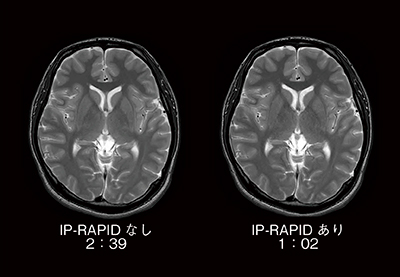

図3および図4は,従来のルーチンプロトコールと,IP-RAPIDを適用して撮像時間を短縮したプロトコールで撮像した,頭部T2横断像と頭部MRAのMIP画像の比較です。IP-RAPIDにより,同程度の画質ながら撮像時間がほぼ半分になっていることがわかります。撮像時間の短縮は検査時間全体の短縮に寄与し,被検者の心身的負担軽減が期待できます。一方,同じ撮像時間ならば,より分解能の高い画像を得ることが可能になると考えられます(図5)。ルーチン画像を短時間で取得することで検査時間枠に余裕が生まれ,異なる断面やシーケンスによる追加撮像が可能になると思われます。このように撮像時間の短縮は検査時間の短縮のみならず,検査内容の充実に対しても貢献し,被検者への手厚い医療が提供できると考えられます。

図3 T2強調画像におけるIP-RAPID有無の比較

撮像時間が半分以下においても,同等の画質が得られている。